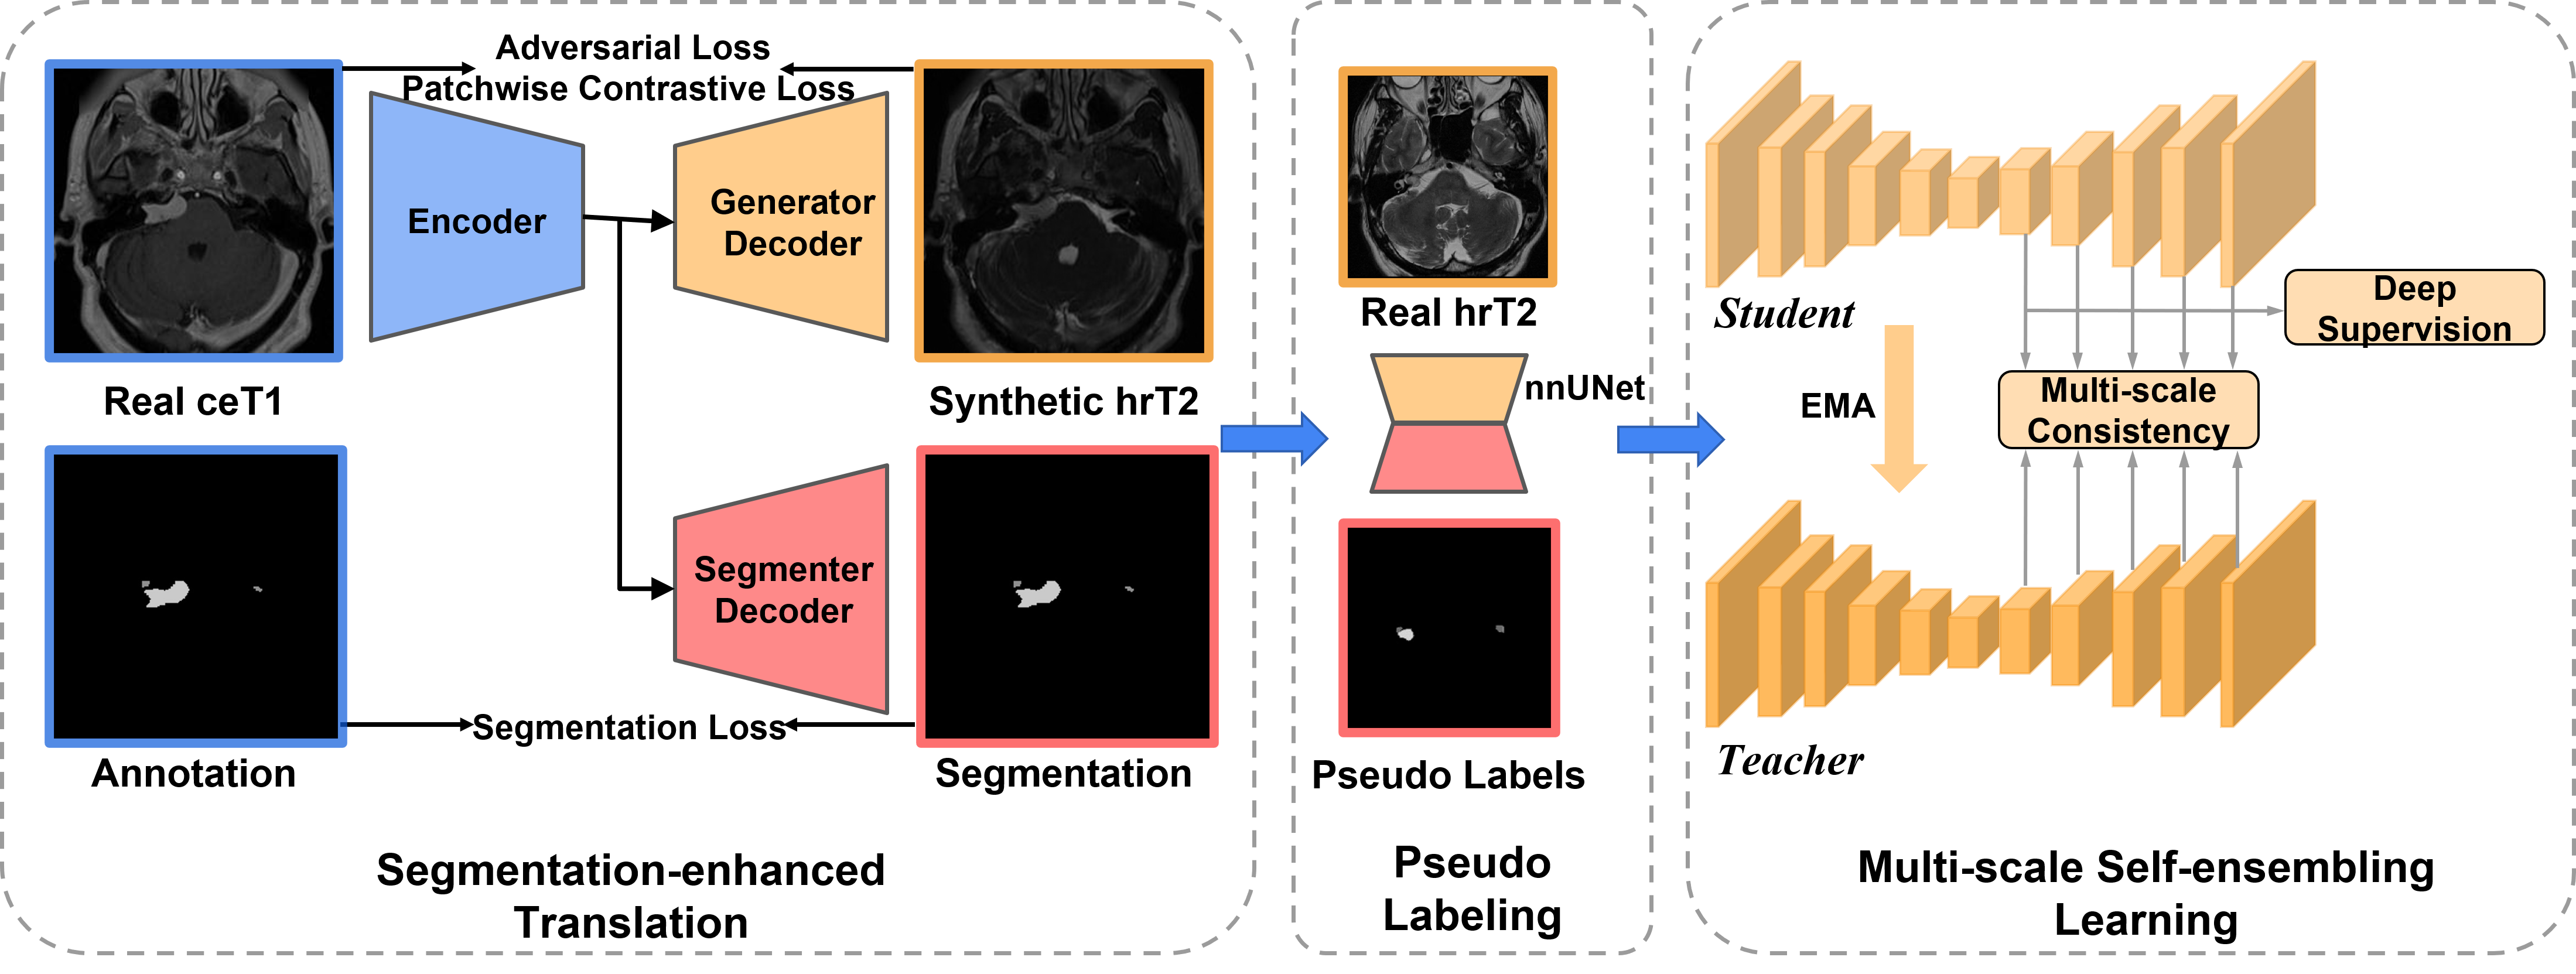

Given an unpaired dataset of two modalities, i.e., annotated ceT1 MRI images and non-annotated hrT2 MRI scans , sharing the same classes (VS and Cochlea), we aim to exploit and for unsupervised domain adaptation to enhance the cross-modality segmentation performance of the VS and Cochlea on hrT2 MRI images. The overview of our UDA framework is shown in Fig. 1.

3.1 Segmentation-enhanced translation

To close the domain gap across the modalities, we first conduct image-level domain adaptation to generate synthetic target samples. In this regard, the model trained on the synthetic target images will be used for VS and Cochlea segmentation on real hrT2 scans. For unpaired image-to-image translation, we adopt the Contrastive Unpaired Translation (CUT) [21] as our backbone since it is faster and less memory-intensive than CycleGAN [36]. Moreover, we enhance the 2D CUT with an additional segmentation decoder for maintaining the structural information of VS and Cochlea (see Fig. 1). Specifically, a ResNet-based generator is used to translate images from the source domain to the target domain, while a PatchGAN discriminator is employed to distinguish between the real and generated images [21]. We follow the SIFA architecture [2] and connect two layers of the encoder, specifically at the last layer and the layer before the last downsampling, with the segmenter decoder to generate multi-level segmentation predictions. The segmentation loss can help the encoder focus more on areas related to the segmentation task and preserve the structure of VS and Cochlea in the translated images. In Fig. 2, we can observe that the modified CUT can better preserve the shape of the VS and Cochlea in comparison with the original CUT framework.

3.3 Multi-scale self-ensembling learning

To further utilize all available data, we propose to take advantage of the self-ensembling network, mean teacher (MT) [28], in which, a teacher model is constructed with the same architecture as the student model, and updated with an exponential moving average (EMA) of the student parameters during training. In our training process, the outputs of the student and teacher models with different perturbations are optimized to be consistent by minimizing the difference using the mean square error (MSE) loss. Inspired by the great success of multi-scale learning in medical image analysis [8, 15, 32], we follow [15] to construct a multi-scale mean teacher (MS-MT) network to leverage multi-scale predictions for deep supervision and consistency regularization. We implement 3D full resolution nnU-Net [13] as the backbone for both teacher and student networks, in which, auxiliary layers are connected to each block of the last five blocks to obtain multi-scale predictions (see Fig. 1).